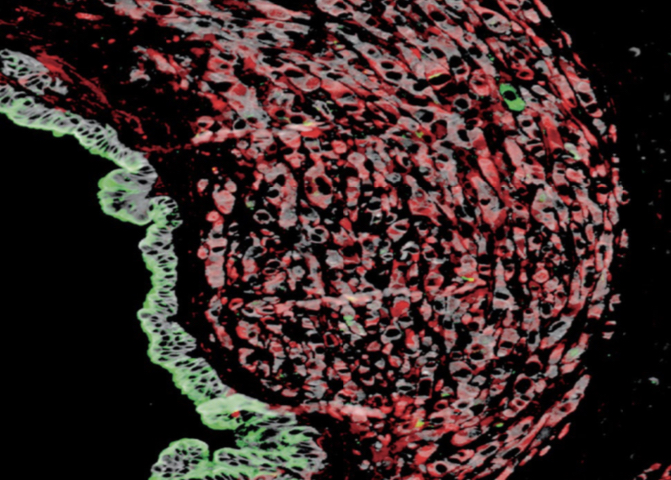

From Surgery to Science: Using Organoids to Study Cancer